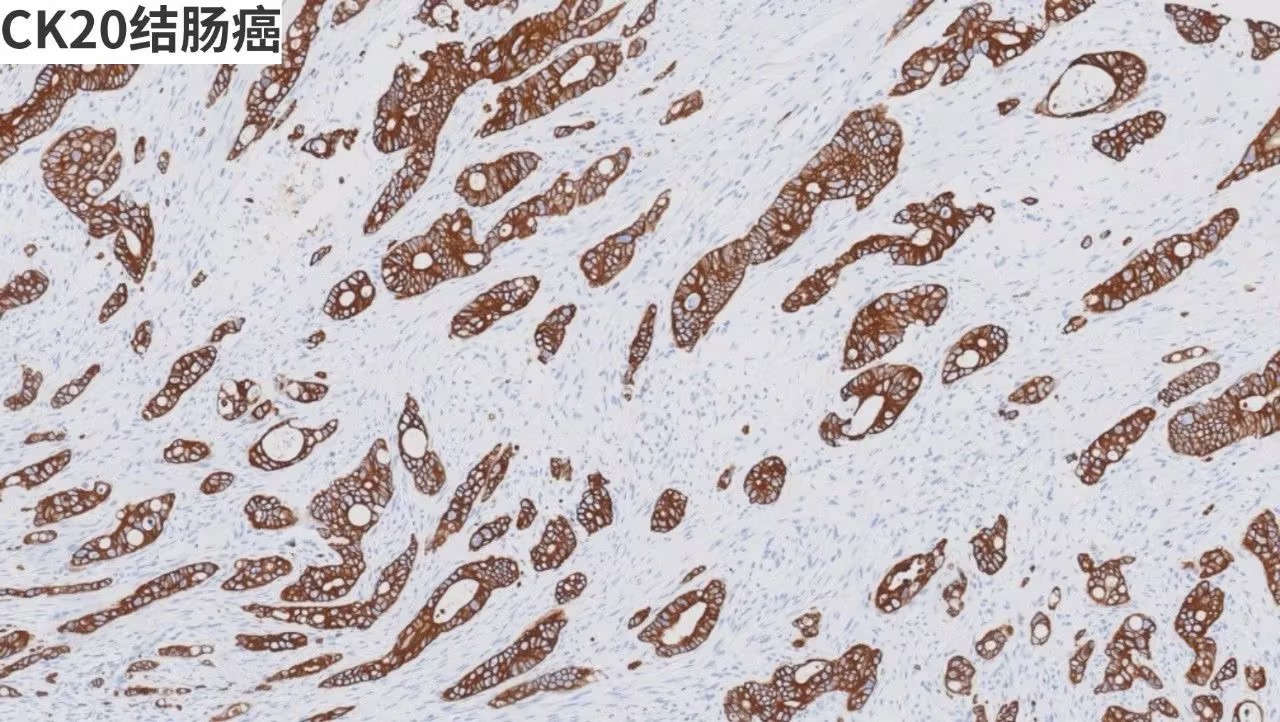

【抗體聚焦】 GATA3/GCDFP - 15/CDX - 2/CK7/CK20/ER/PR

產(chǎn)品染色圖賞析